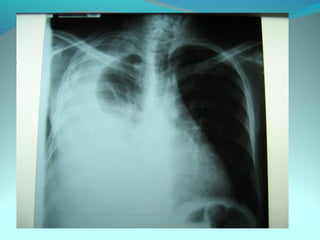

Opacité triangulaire a base cardiaque a sommet

axillaire dense et homogène

Par ailleurs on note

Une opacité plus dense que celle arrondie de 3cm de

diam hilaire gauche ;une surélévation de la coupole

diaphragmatique gauche é poche a aire gastrique

DIAGNOSTIC :

ADP hilaire gauche avec trouble de ventilation

Surelevation de la coupole G et de la poche gastrique

avec de clarté le médiastin

DIAGNOSTIC:

Hernie diaphragmatique paralysie du diaphragme